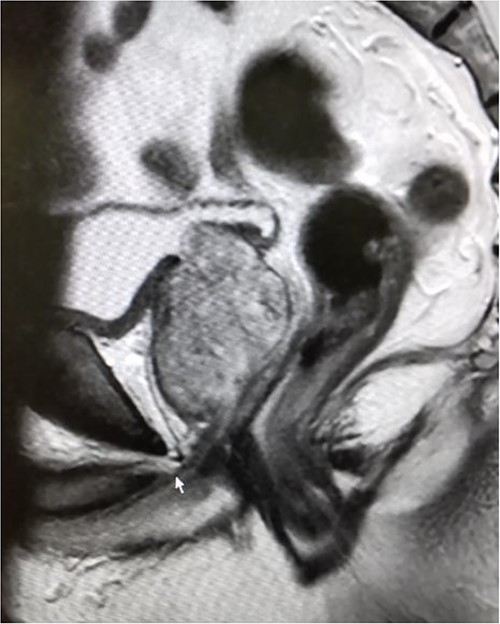

The patient was a 72-year-old man with BPH, a prostate volume of 50.0 ml, and high middle-lobe hypertrophy (Fig. 1). His initial prostate-specific antigen level was 14.94 ng/ml, and preoperative magnetic resonance imaging revealed PI-RADS III in the left peripheral zone. Prostate biopsy was 1/10 positive and revealed adenocarcinoma with a Gleason score of 4 + 4 = 8 (cancer core length 5/15 mm) in the left peripheral zone. Following the biopsy, the patient had a urethral catheter inserted as he could not urinate due to the BPH. The patient had a history of hypertension, true polycythemia vera, and cerebral infarction; further, he had an Eastern Cooperative Oncology Group performance status of 0 and was taken off antiplatelet medications before surgery.

Magnetic resonance imaging before surgery showing BPH with middle lobe hypertrophy.